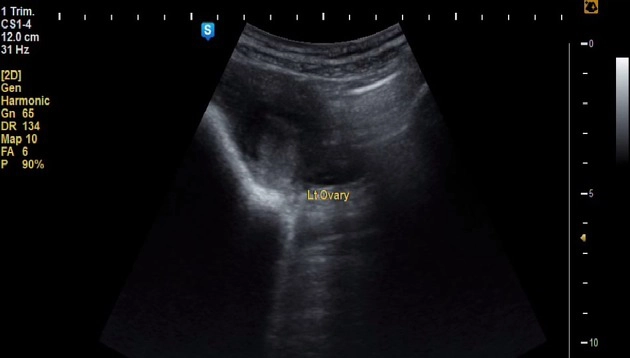

Thai ngoài tử cung ở buồng trứng (Ovarian ectopic pregnancy)

• Thai ngoài tử cung ở buồng trứng (Ovarian ectopic pregnancy)